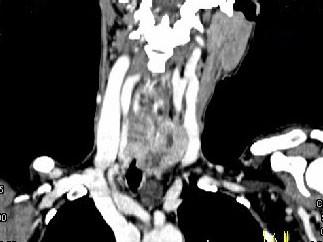

问题 女,50岁,左下颈部扪及一质硬、表面高低不平的包块,肿块逐渐增大,现感吞咽困难,CT如图所示,最可能诊断为()

选项 A.甲状腺癌 B.食管癌 C.喉癌 D.甲状腺原发淋巴瘤 E.颈部神经鞘瘤

答案 A